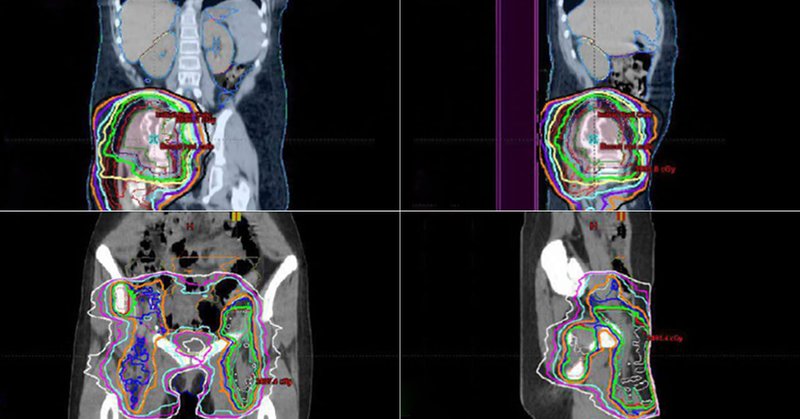

A preliminary study by our #PediatricOncology experts linked pelvic external beam radiation therapy to increased risk for late effects impacting lower urinary tract function in cancer survivors. #ChildhoodCancer

Study turns focus to late effects of childhood cancer treatment.